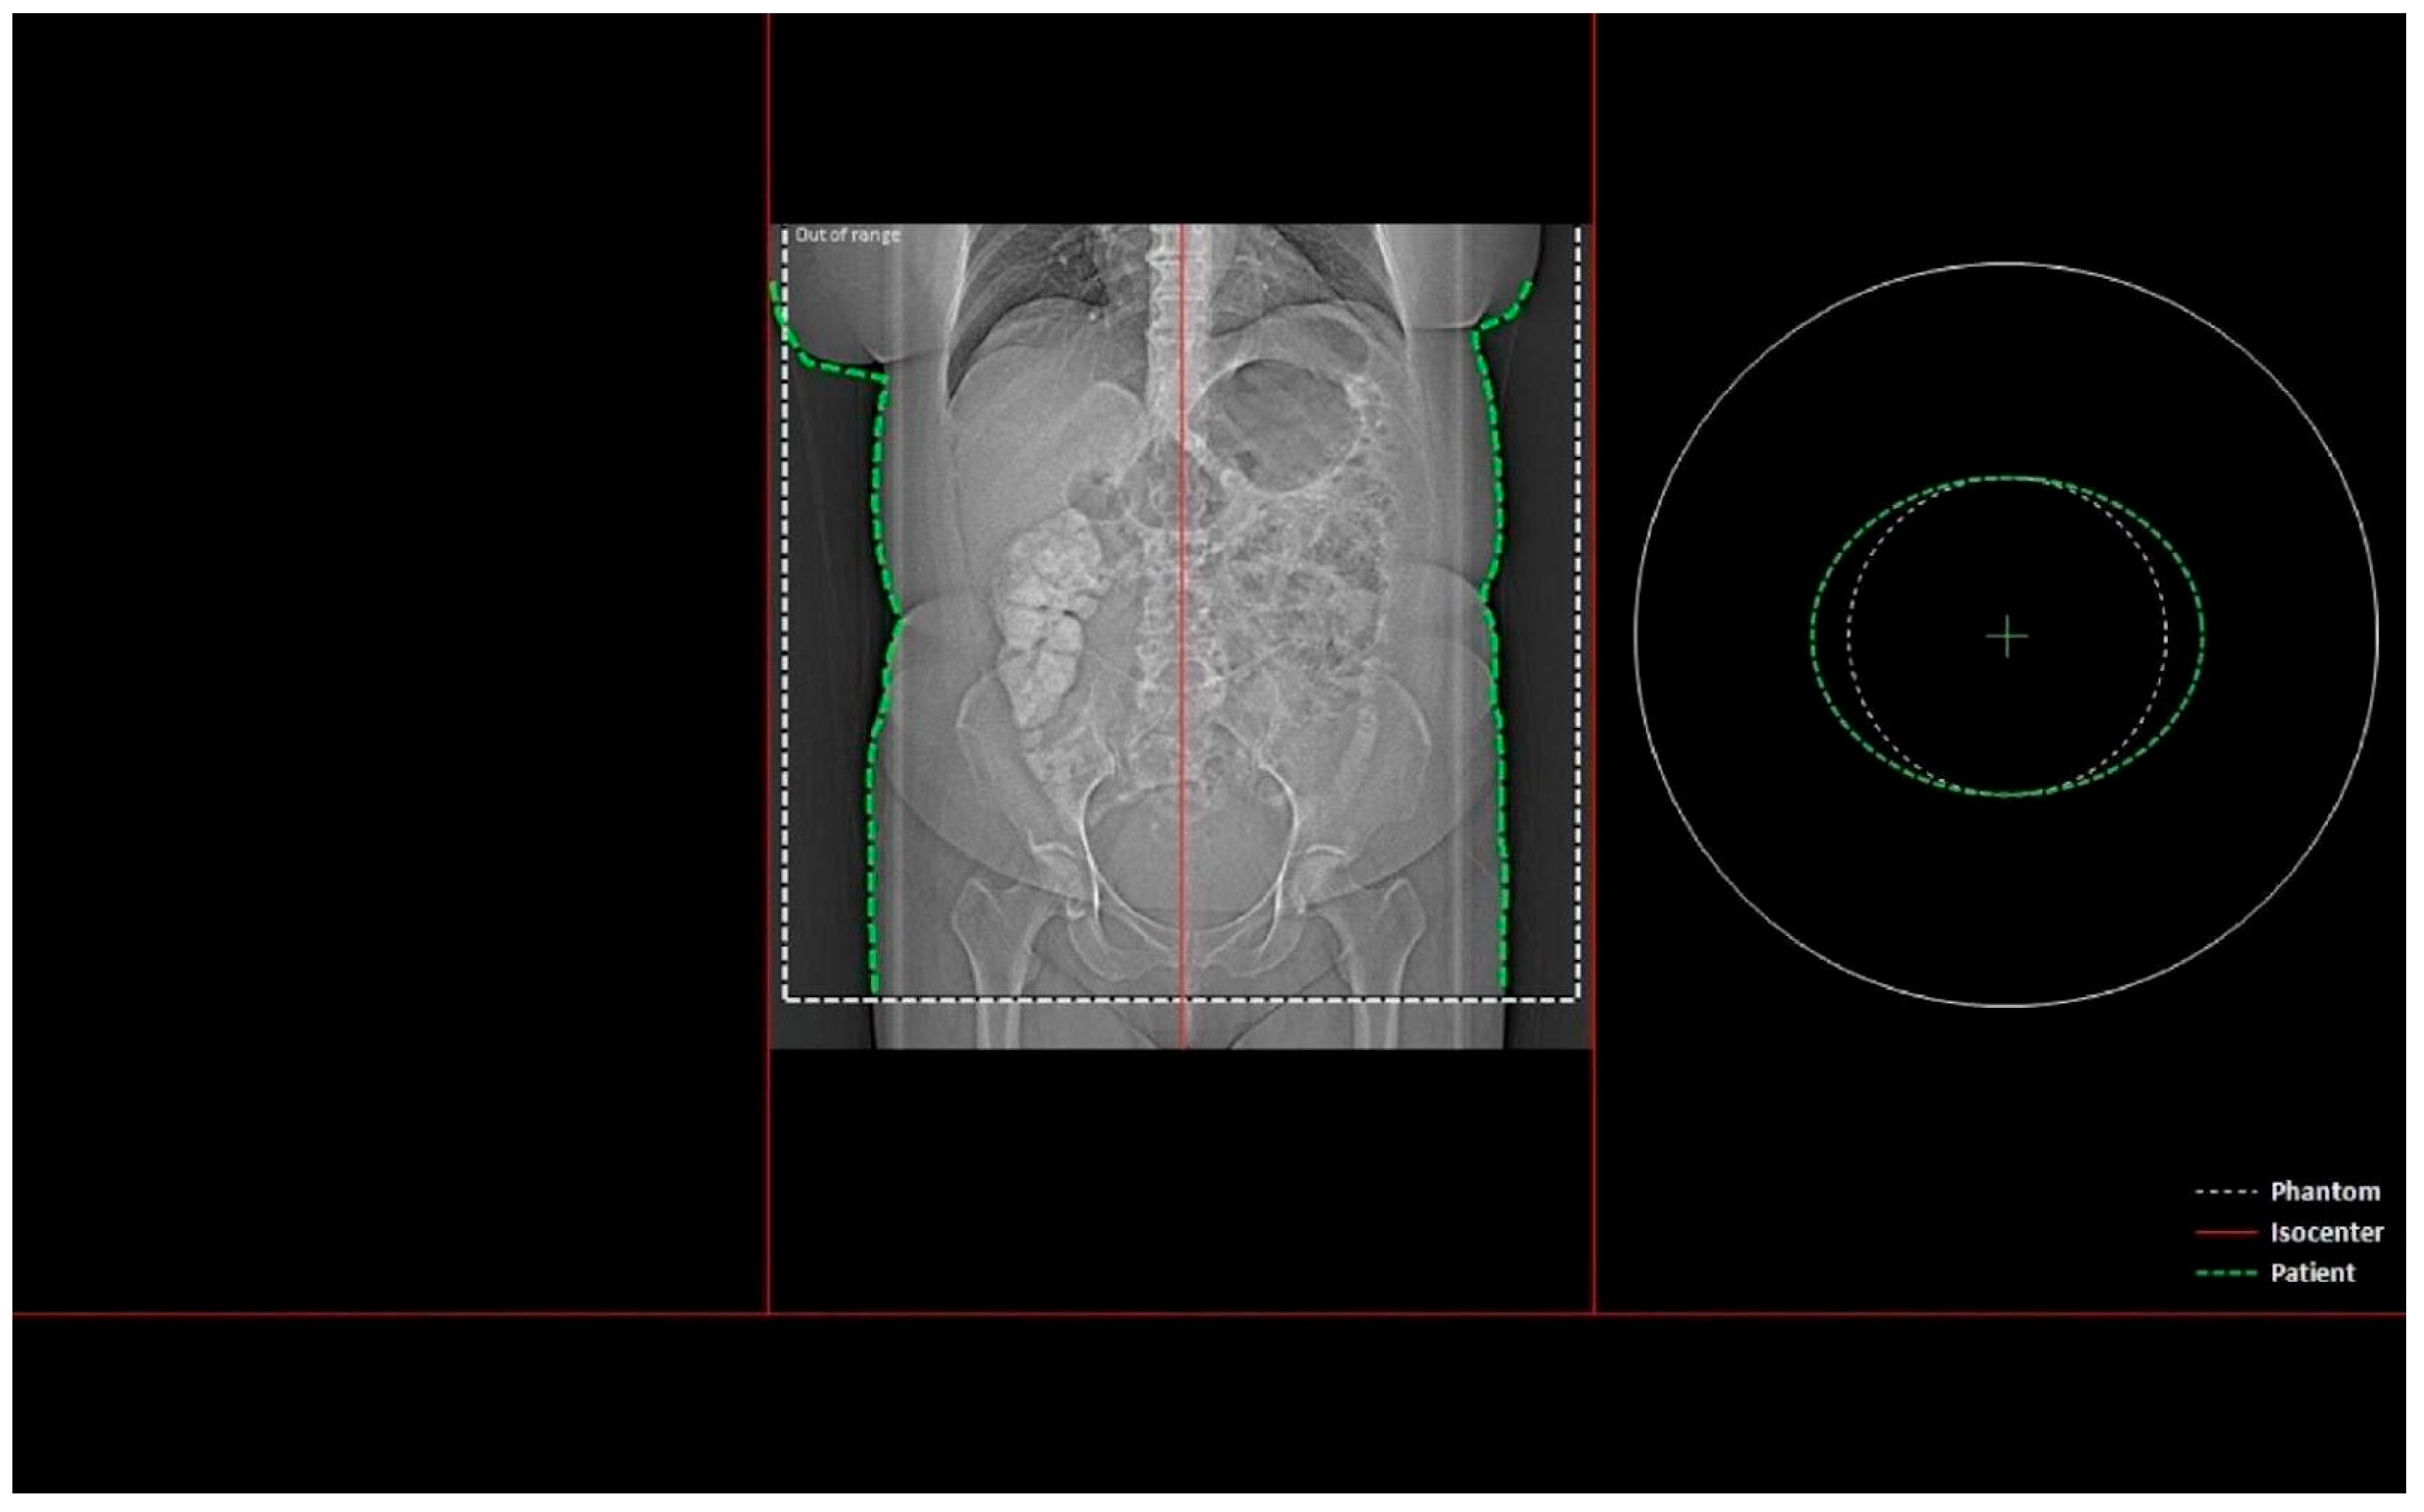

- Whether the patient was in the isocenter—Figure 1 shows the patient outside the isocenter, while Figure 2 shows the patient inside the isocenter.

Figure 2. Image from the Dose&Care system showing patient placement in the isocenter.

For the analysis, studies performed using a three-phase liver protocol in 258 patients (including 135 women and 123 men) were used. Due to missing data in some cases, the number of patients included may vary across individual statistical analyses. All examinations were performed using a Siemens SOMATOM Definition Edge scanner. The study group consisted of 80 abdominal and 178 abdominal and pelvic examinations. In our study, the isocenter shift did not exceed 5 cm. Patients were classified as being “in the isocenter” if the patient’s isocenter coincided with the scanner’s isocenter; otherwise, they were assigned to the “not in the isocenter” group.